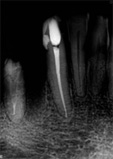

antes depois